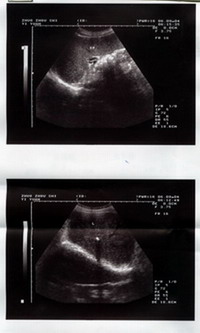

患者:王某 男 58岁 河北省雄县人 于2004年9月8日中午11时来诊。 主治:右肝内胆管结石合并左输石 主诉:左侧少腹疼痛伴腹胀4天 病史:患者于半年前突发左少腹疼痛一次,后症状消失;于4天前复出现左少腹胀痛,伴满腹胀鼓。于涿州市医院查B超示:1.右肝内胆管结石 2.脾轻大3.胰、胆未见异常 化验:肝功GPT40单位 现状:左少腹胀痛,间断出现右肝区疼痛 叩诊:左少腹压刺痛,右侧肝区叩击痛 治疗情况: 本所根据所发症状,确定右肝内胆管结石及脾轻大不排除,但主要为左侧输尿管异常,怀疑左输石存在。即查B超发现:1.右肾轻度积水2.左侧输尿管中下段扩张伴结石 初诊治疗后即觉左少腹及腹胀减轻。 三诊:诉出现尿频症状及尿中可见浑浊。 五诊:腹胀基本消失 九诊:肝区无叩击痛,复查B超:肝内胆管结石影像消失。 十四诊:无不适症状,复查B超未见异常。 以下为检查报告图片: